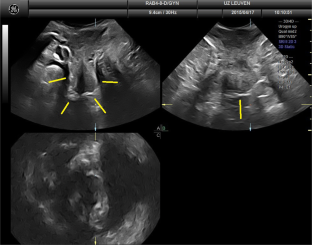

There were 17 women in the PP and 25 in the PVDF mesh group, without differences in baseline demographics. None had significant prolapse, recurrence, symptoms, or complications. On TPUS, mesh was visible in all patients both caudally (perineal) and cranially but was more echogenic in the PVDF mesh group. Mesh length from distal to proximal that was visible on TPUS was longer for PVDF mesh, for both anterior and posterior vaginal arms (all P < 0.05), and for mesh above the vaginal apex (P = 0.002). The inferior aspects of the mesh showed areas of double mesh layers, suggesting folding in 80% of women in both groups, without symptoms.

Fig. 4